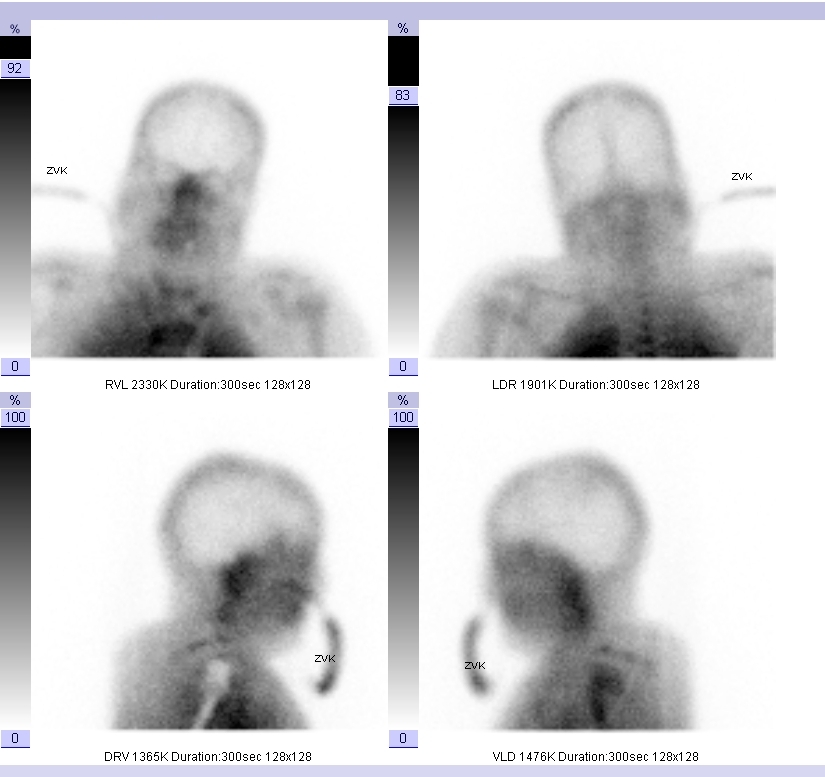

Hirntod: Fehlende Hirnperfusion in der Hirnperfusionsszintigrafie